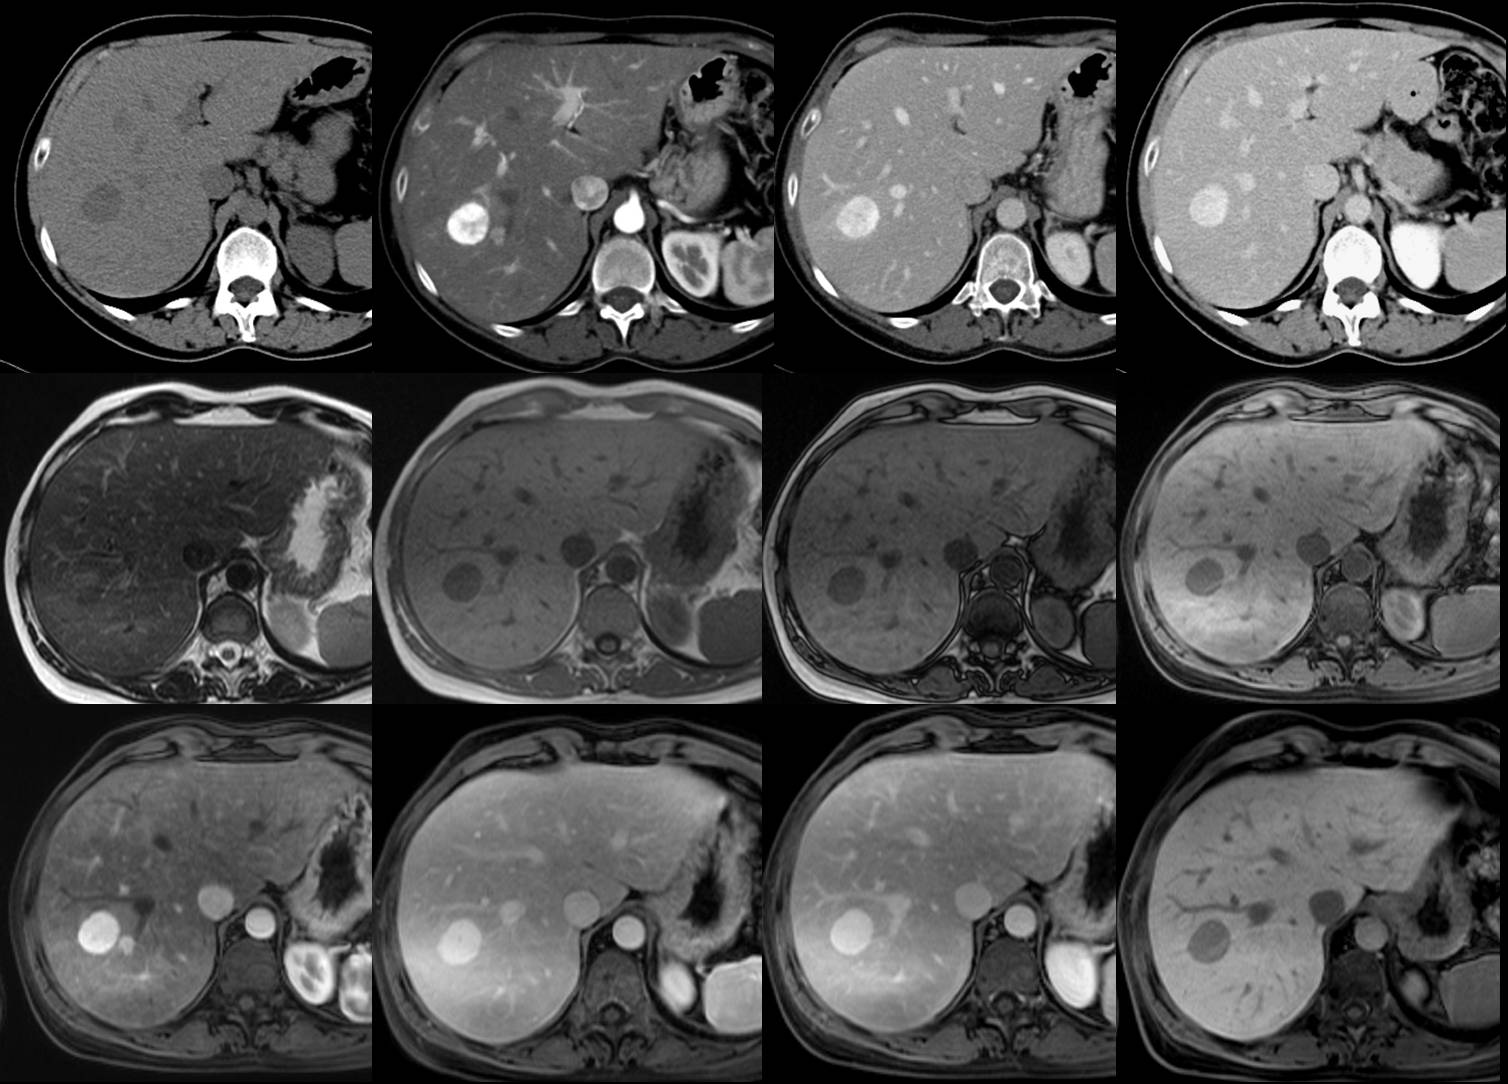

La procedura consiste, secondo quanto spiegato dall’equipe, nell’introduzione mirata di una sonda d’acciaio di calibro sottile (1,6mm) all’interno della lesione cancerosa del fegato, sotto la guida dell’ecografia; l’estremita’ del dispositivo emette microonde all’interno del tumore, che producono calore e ‘bruciano’ le cellule cancerose per un diametro predefinito di circa 3,5 per 5 cm.

La tecnica consente di trattare tumori di piccole dimensioni, sia primitivi che metastatici al fegato, con una durata piu’ breve (10 minuti circa) rispetto alle terapia per cutanee tradizionali (radiofrequenza) e si pone come alternativa alla chirurgia nei casi in cui l’intervento non sia praticabile per motivi tecnici o per l’eta’ e le condizioni cliniche del paziente. L’equipe diretta da Solinas esegue procedure interventistiche per via ecoguidata, quali biopsie addominali e trattamenti dei tumori del fegato, gia’ dal 1985, con una casistica di oltre 6000 casi provenienti dall’Umbria e da fuori regione.